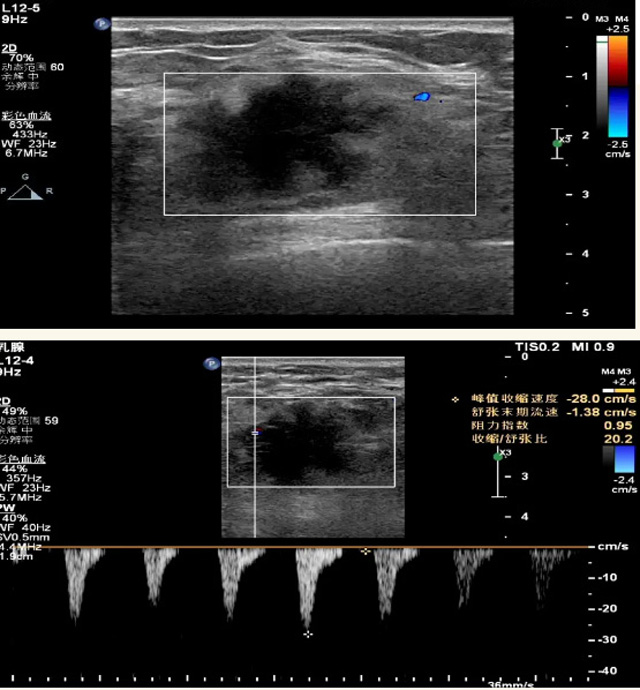

乳腺B超檢查無輻射,對囊性病變敏感,可以實(shí)時(shí)觀察病灶。超聲引導(dǎo)活檢跟手術(shù)前的定位。就是它對于微小的鈣化查出率比鉬靶稍微差點(diǎn)。磁共振MRI檢查也是是沒有輻射的,對備孕跟已經(jīng)懷孕的人士比較友好。不用擔(dān)心這個(gè)輻射影響胎兒問題。對乳腺病灶敏感性較高,致密乳腺病灶、乳腺癌的復(fù)發(fā),準(zhǔn)確鑒別囊性及實(shí)性病變。可以幫助臨床醫(yī)生判斷惡性、良性病變。但是MRI磁共振對微小鈣化不明顯,微鈣化還是鉬靶靠譜點(diǎn)。檢查時(shí)間比較長,有偽影的影響。費(fèi)用相對B超,鉬靶高很多。

乳腺B超